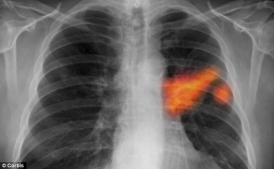

Даже на первый взгляд вполне здоровые курильщики создают в своих легких питательную среду для неизлечимого недуга. У них у всех врачи обнаруживают ранние признаки повреждения клеток, приводящего к раковым заболеваниям. В то время, как все анализы и даже рентген показывают, что эти люди совершенно здоровы, клетки дыхательной системы уже имеют повреждения.

В клетках, расположенных на поверхности легких, включаются гены, ассоциируемые с раком. Клетки теряют контроль за своим развитием, и в них нарастает беспорядок. Об этом говорит автор исследования профессор генетической медицины Медицинского колледжа Уайлла Корнелла доктор Роналд Кристел.

Он изучил состояние клеток здоровых курящих и некурящих людей и выявил вполне очевидный изъян в легких всех курильщиков. Врачей особенно настораживает то, что сигаретный дым включает ген эмбриональных стволовых клеток в дыхательных путях, что обычно происходит при развитии агрессивных форм рака. Мы были удивлены обнаружением у курящих людей этих работающих генов, которые не функционируют в здоровых легких.

Доктор Кристел оговаривается, что такое состояние клеток не означает, что у человека обязательно должна развиться болезнь, однако оно создает благоприятную почву для возникновения смертельного недуга.